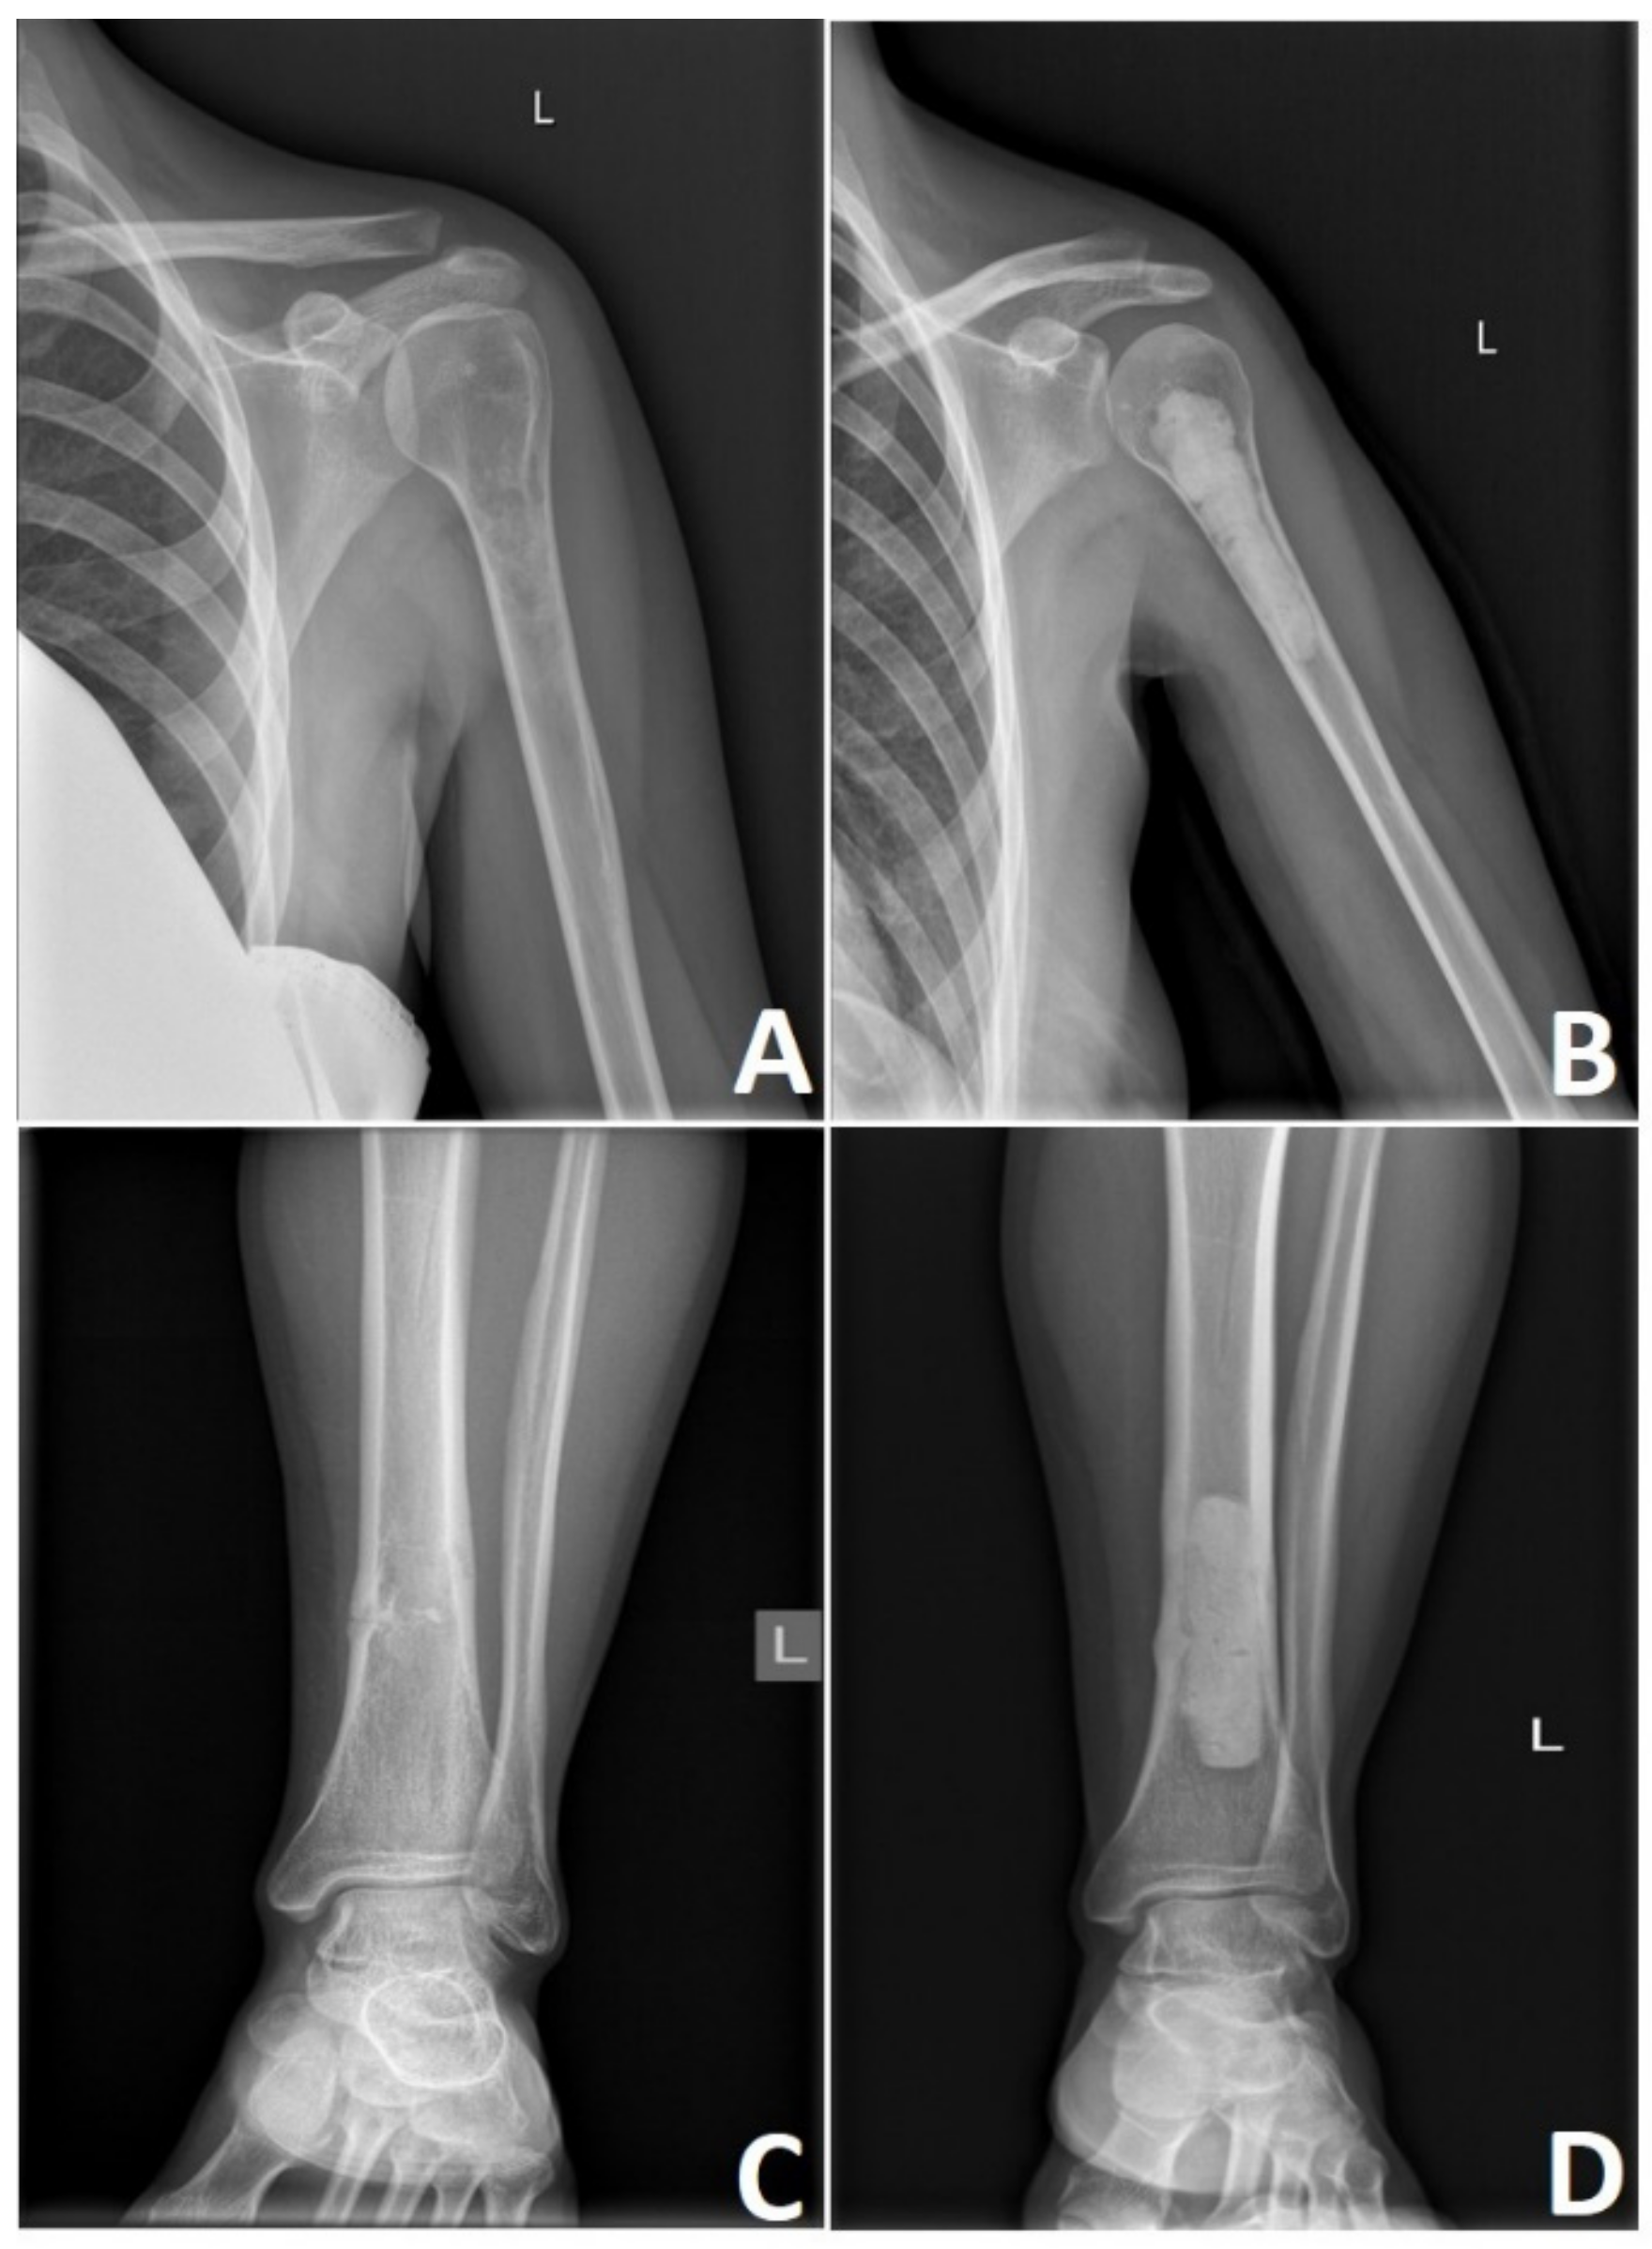

Poor vascularity of the tumor and low percentage of dividing cells significantly contribute to this tumor’s chemo and radiotherapy resistance [12,125]. There is a difference in treatment scenario between low-grade and high-grade CHS and axially and extremity located tumors. Aggressive high-grade tumors require aggressive surgical treatment, where adequate wide surgical margins remain the paramount factors of future results [126]. According to Fiorenza et al. [127], independent risk factors for LR are inadequate surgical margins and tumor size greater than 10 cm. Keeping in mind the low metastatic potential of the grade 1 CHS, it is currently apparent that wide surgical excision of small asymptomatic lesions that can be easily curetted or excised should not be a primary choice. In many cases, these tumors may be treated with contaminated margins to reduce operative morbidity and reduce patient survival. Of course, it is not a case for higher-grade CHSs where a wide excision is a necessary form of therapy [128] (Figure 6).

Figure 6.

High-grade chondrosarcoma of the left scapula. Preoperative X-ray of the G3 scapular chondrosarcoma (A) and after en bloc upper interscapulothoracic humeral resection (B) This particular procedure known as Tikhoff-Linberg is a limb-sparing surgical option for tumors in and around the proximal humerus and shoulder girdle and an alternative treatment to forequarter amputation; however, is associated with poor cosmetic appearance (C) that can gradually change over the years depending on soft tissue contracture and scar tissue formation (D). Photos by Bartłomiej Szostakowski.

Figure 7.

Low-grade chondrosarcoma. Rarely symptomatic lesions are discovered incidentally on X-rays after injury to the extremity (A,C). Meticulous curettage of G1 chondrosarcomas and polymethyl methacrylate cementoplasty remains the mainstay of treatment (B,D). Photos by Bartłomiej Szostakowski.

High-grade CHS lesions of the long bones usually require resection followed by limb-sparing surgery. This involves reconstruction with a modular endoprosthetic replacement, custom-made prosthesis, or bone graft reconstruction (Figure 8). In rare occasions, the size or location of these tumors necessitates a more radical approach where amputation of the affected limb remains the treatment of choice. Bingold has reported one of the first resections of the long bone in CHS, followed by a custom-designed prosthetic replacement. After resection of the proximal femoral low-grade CHS, he reported prosthetic reconstruction that spans across 43 years with several revisions [136]. Nowadays, prosthetic replacements for low-grade CHS are advocated only in locally advanced lesions where curettage or marginal resection is not an option. Prosthetic reconstruction in high-grade CHS remains to be standard with multiple options available [136,137].

Figure 8.

High grade locally advanced acral chondrosarcoma. Preoperative image of the locally advanced G2 (A) and G3 (B) chondrosarcoma of the left proximal femur. Reconstruction with modular endoprosthetic replacement (C,D). Photos by Bartłomiej Szostakowski.